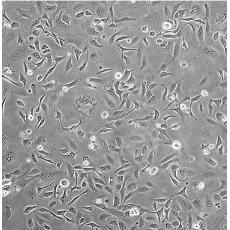

SK-OV-3 [SKOV3]

產(chǎn)品名稱 SK-OV-3 [SKOV3]

中文名稱 人卵巢癌細(xì)胞

組織來(lái)源 卵巢漿液性囊腺癌;腹水轉(zhuǎn)移;女性

生長(zhǎng)特性 adherent

形態(tài)特征 epithelial

細(xì)胞描述 SK-OV-3 cells are resistant to tumor necrosis factor and to several cytotoxic drugs including diphtheria toxin, cis-platinum and adriamycin.